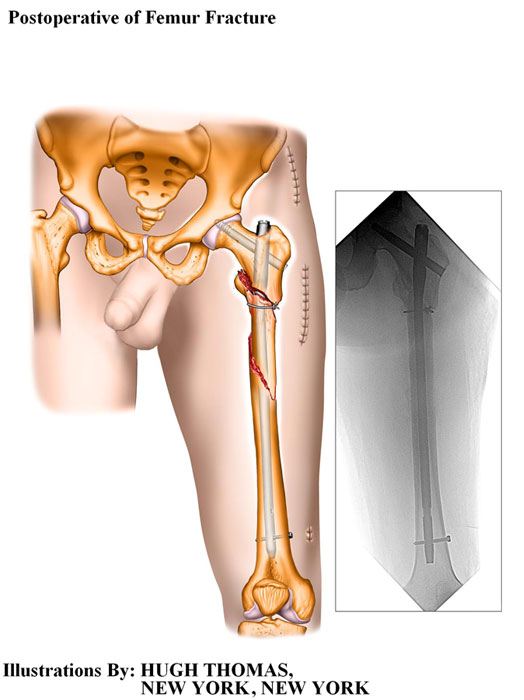

The medical illustrations on this page are examples of the details the attorneys at the Law Offices of William Cafaro prepare for jury presentations.